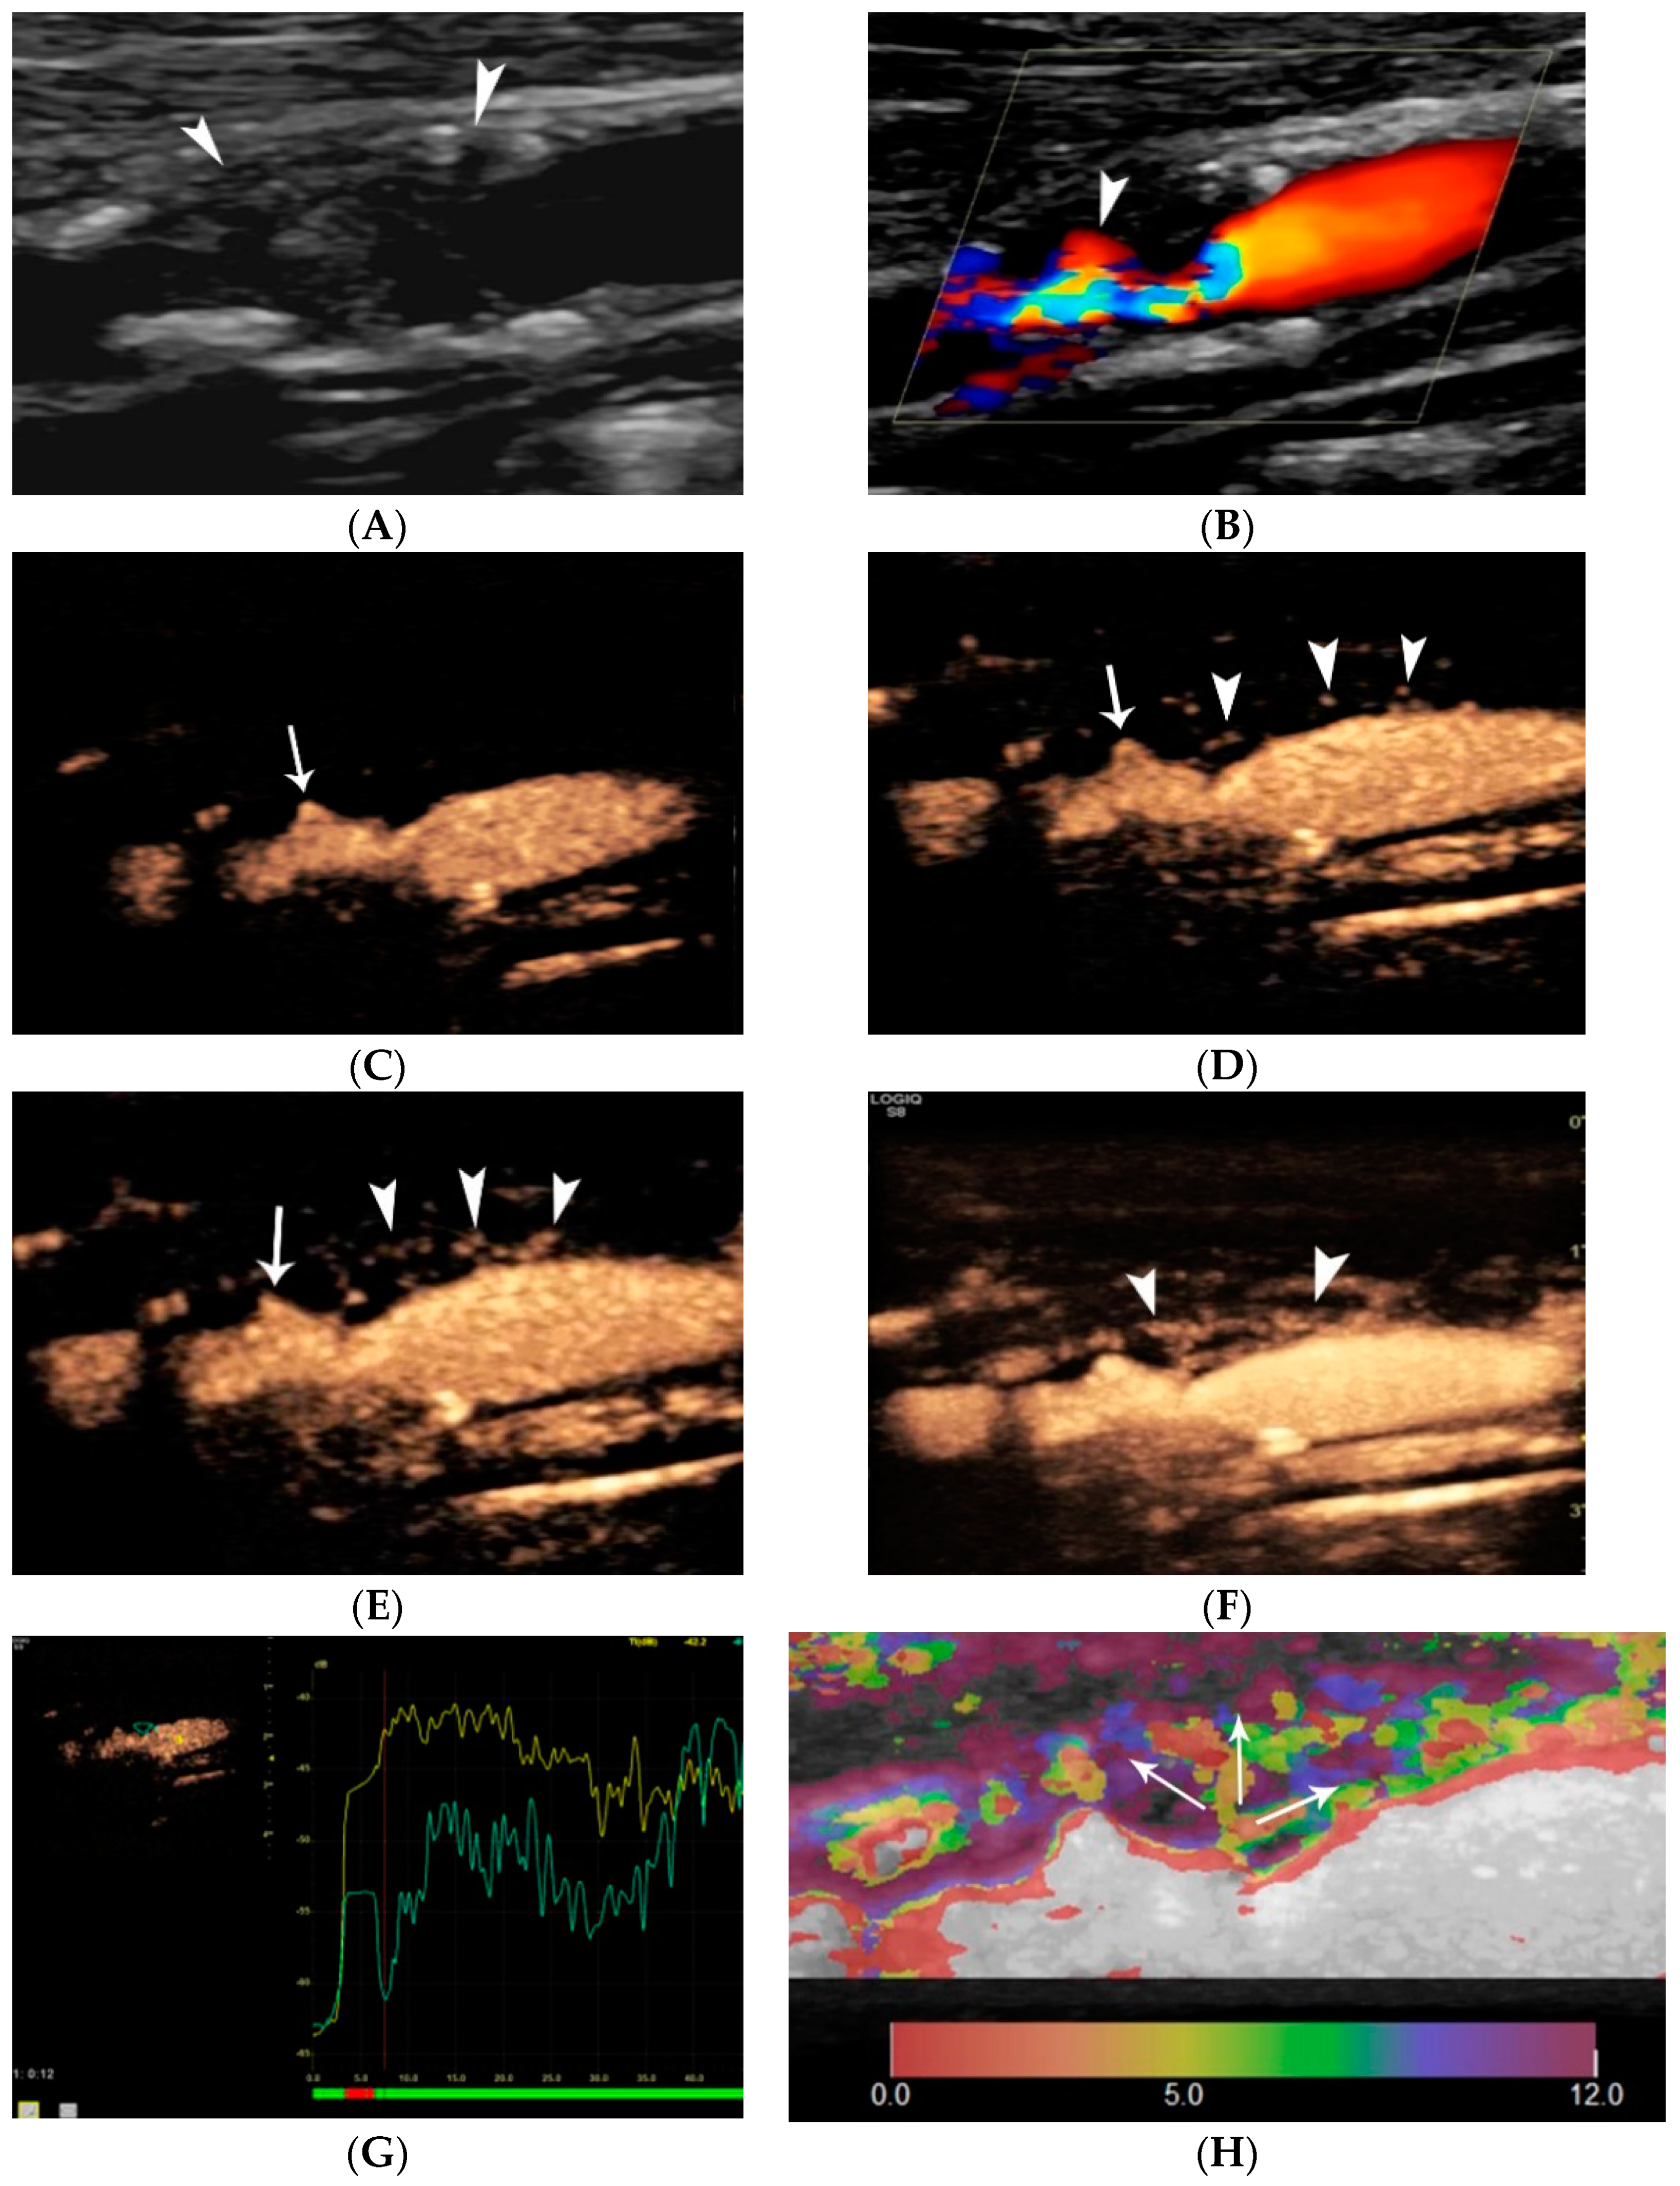

- Heliopoulos, J.; Vadikolias, K.; Piperidou, C.; Mitsias, P. Detection of carotid artery plaque ulceration using 3-dimensional ultrasound. J. Neuroimaging Off. J. Am. Soc. Neuroimaging 2011, 21, 126–131. [Google Scholar] [CrossRef] [PubMed]

- Madani, A.; Beletsky, V.; Tamayo, A.; Munoz, C.; Spence, J.D. High-risk asymptomatic carotid stenosis: Ulceration on 3D ultrasound vs. TCD microemboli. Neurology 2011, 77, 744–750. [Google Scholar] [CrossRef]

- Rafailidis, V.; Chryssogonidis, I.; Tegos, T.; Kouskouras, K.; Charitanti-Kouridou, A. Imaging of the ulcerated carotid atherosclerotic plaque: A review of the literature. Insights Imaging 2017, 8, 213–225. [Google Scholar] [CrossRef]

- Rafailidis, V.; Charitanti, A.; Tegos, T.; Rafailidis, D.; Chryssogonidis, I. Swirling of microbubbles: Demonstration of a new finding of carotid plaque ulceration on contrast-enhanced ultrasound explaining the arterio-arterial embolism mechanism. Clin. Hemorheol. Microcirc. 2016, 64, 245–250. [Google Scholar] [CrossRef]

- Rafailidis, V.; Chryssogonidis, I.; Xerras, C.; Nikolaou, I.; Tegos, T.; Kouskouras, K.; Rafailidis, D.; Charitanti-Kouridou, A. A comparative study of color Doppler imaging and contrast-enhanced ultrasound for the detection of ulceration in patients with carotid atherosclerotic disease. Eur. Radiol. 2019, 29, 2137–2145. [Google Scholar] [CrossRef]